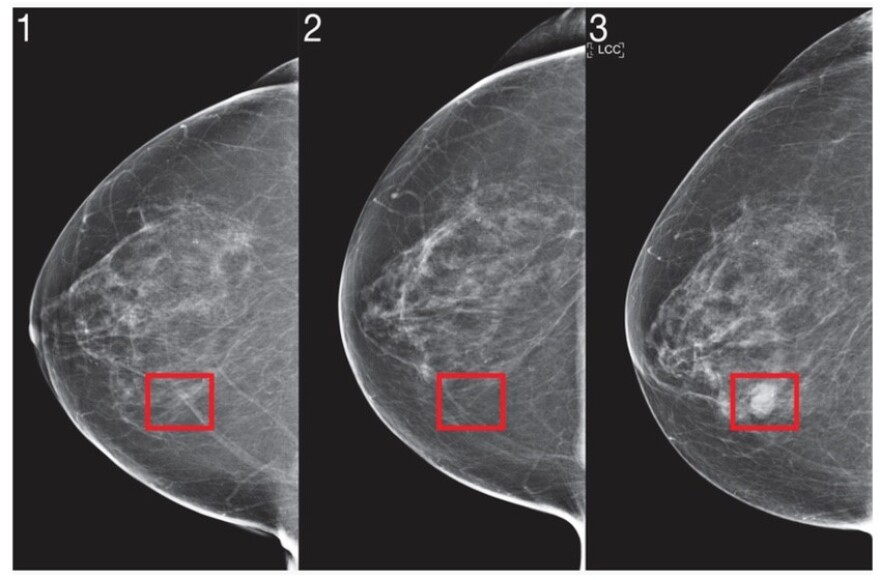

MIT researchers use artificial intelligence to predict breast cancer.

Regina Barzilay got involved seven years ago when she was diagnosed with breast cancer. She’d had mammograms every year for three consecutive years, so she wondered why the cancer hadn’t been detected earlier. And since she happened to be a professor of artificial intelligence at Massachusetts Institute of Technology, she teamed up with Harvard Medical School researchers to find out why.

“When I looked back three years, I actually saw the beginning of the cancer was there,” Barzilay said. “It was even more there in the second year and it was even more there in the third year that they can diagnose it.”

Radiologists couldn’t identify the early markers. But a computer using AI can — because it’s able to scan hundreds of thousands of images and teach itself to detect the early signs. Barzilay has now developed a way to use AI to identify those at highest risk of developing breast cancer, and Massachusetts General Hospital is using it.

“I think (the) human mind cannot fully utilize all this information. It’s impossible,” she said. “And this predictive capacity by knowing what’s to come is what will hopefully improve their outcomes and reduce the cost.”